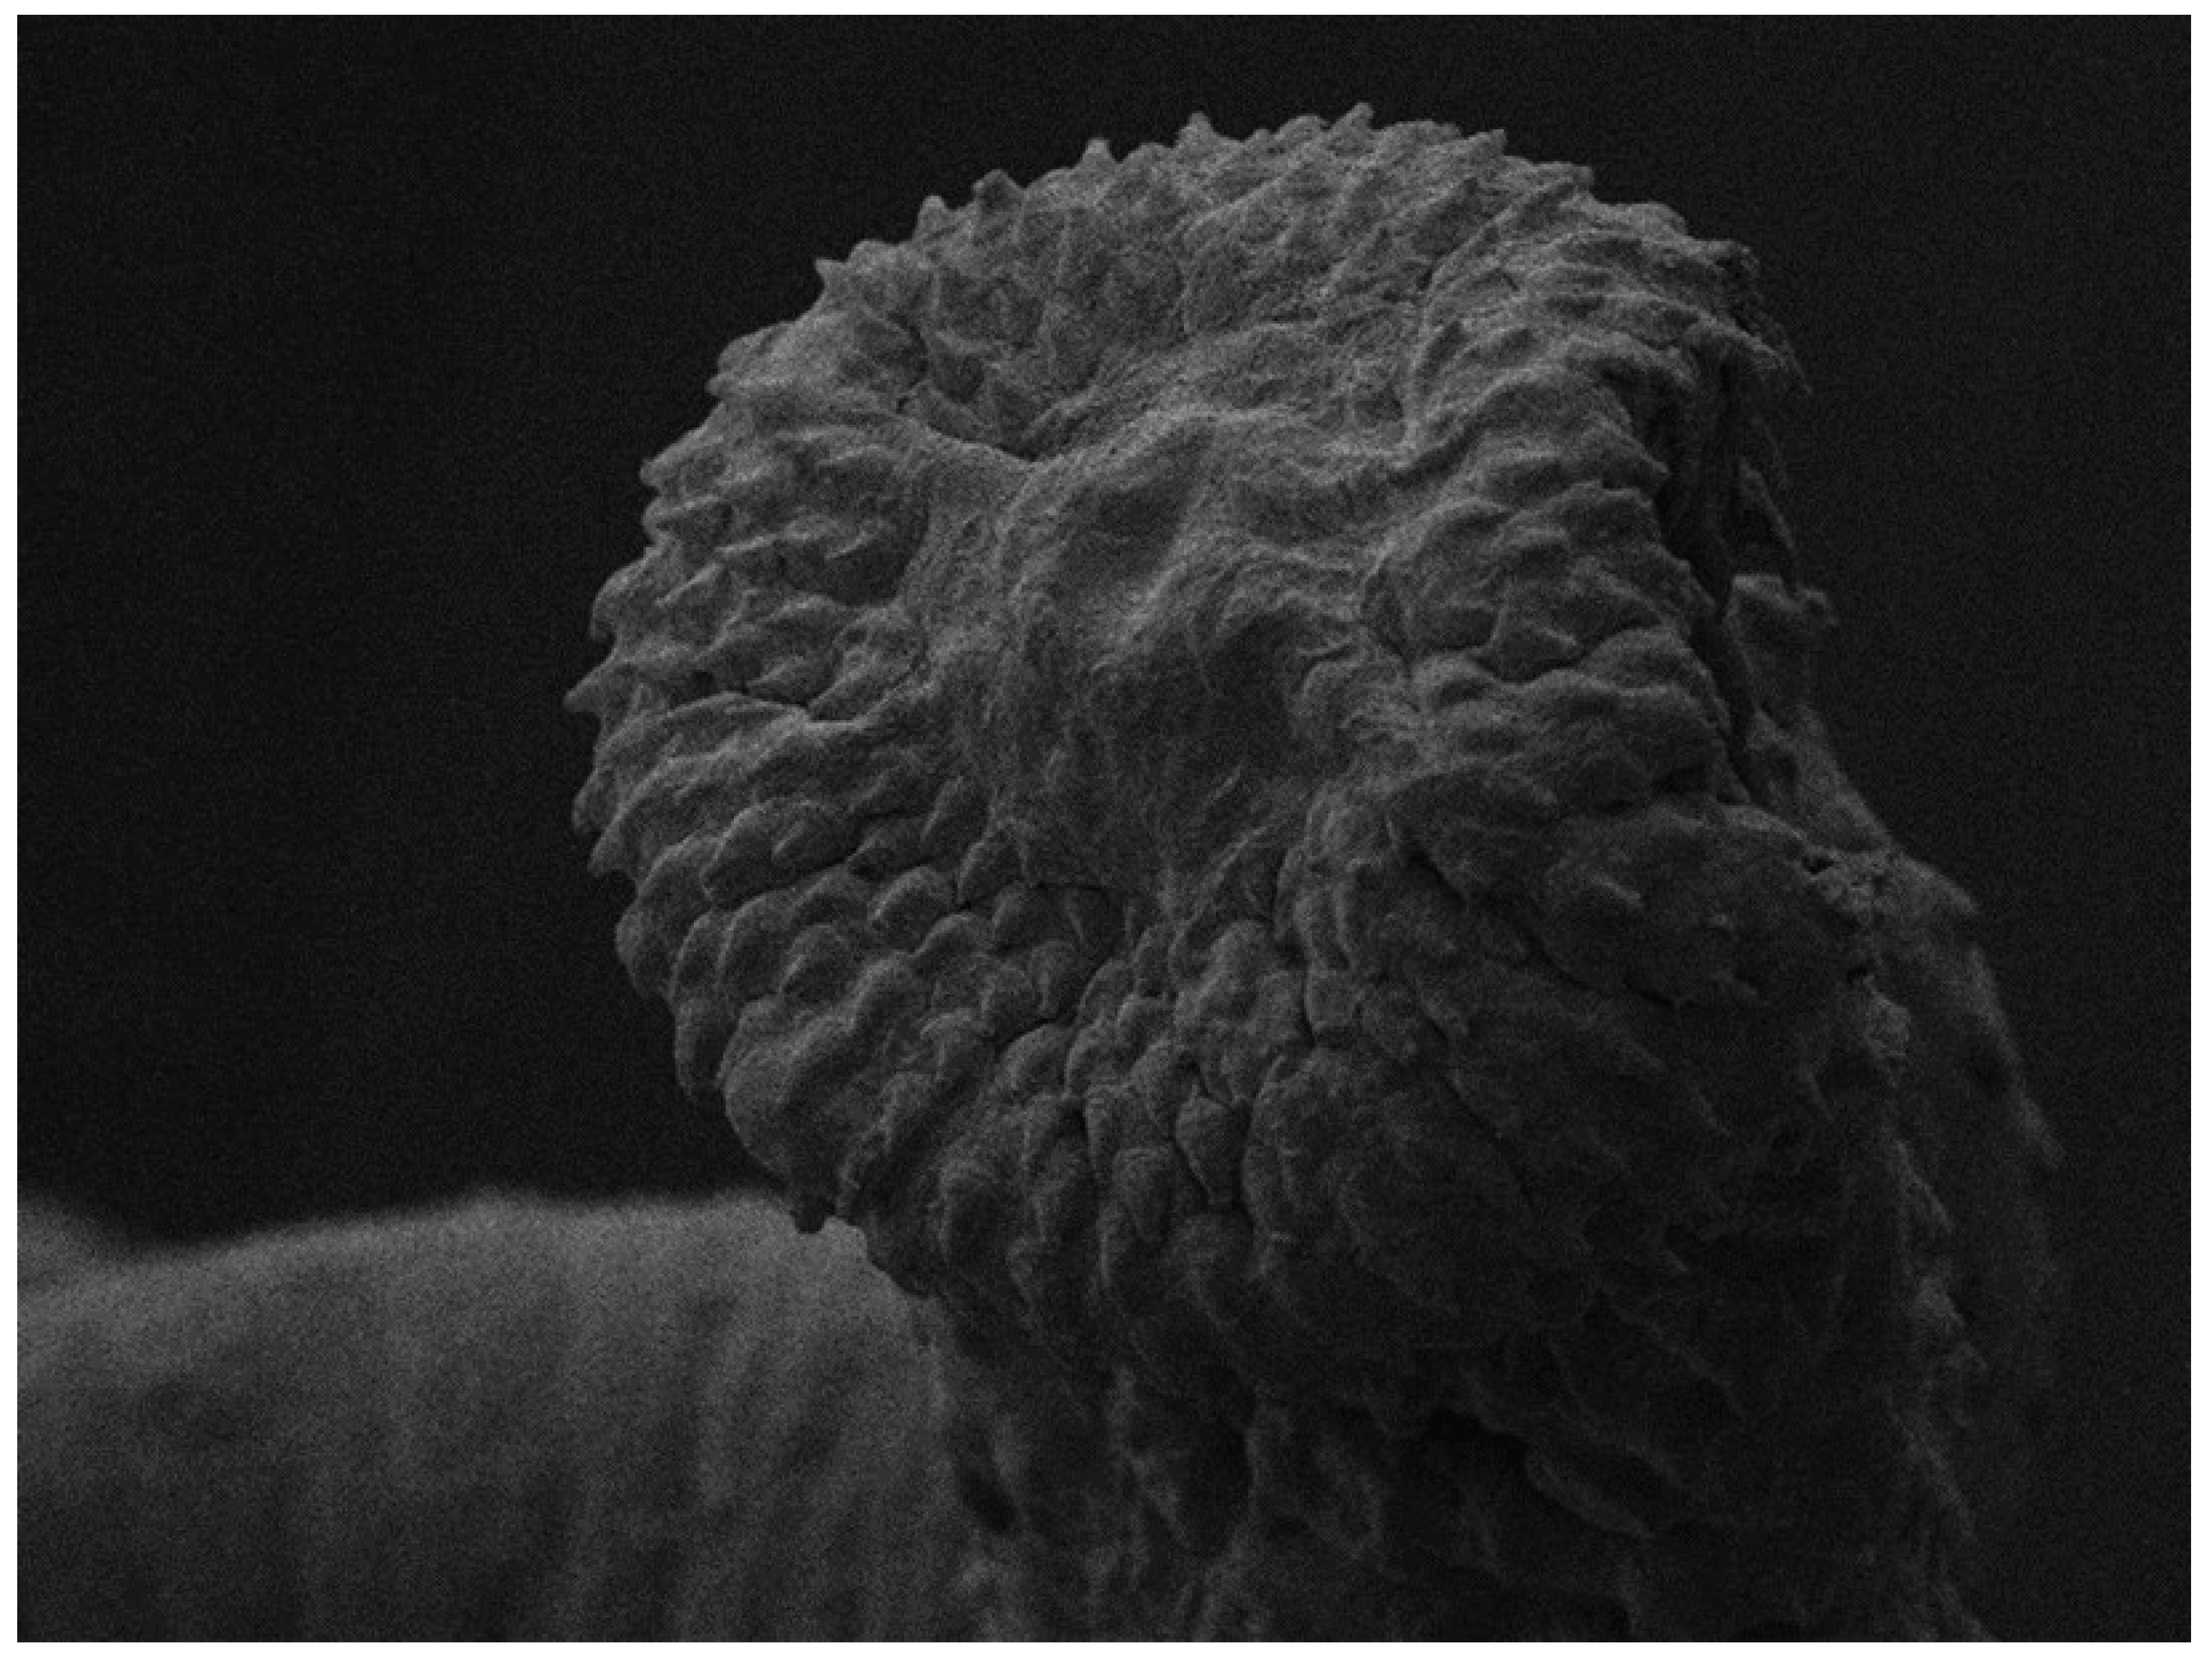

3.2.4. Scanning Electron Microscopy (SEM)